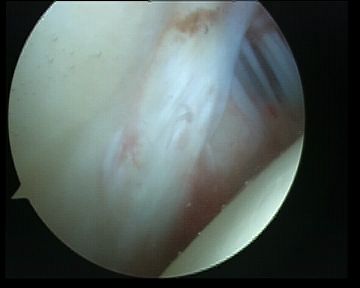

| Inferior glenohumeral ligament (IGHL) | |

|---|---|

|

Origin: Inferior 2/3 glenoid and labrum Insertion: Anatomical neck humerus

Anterior band: antero-inferior glenoid to 3 o'clock Posterior band: postero-inferior glenoid to 9 o'clock Axillary pouch between two bands |

| Most important ligament in terms of stability | Stabilizes arm at 90 degrees of abduction |

Anterior IGHL glenoid attachment |

IGHL humeral attachment |

Inferior recess

Loose body in inferior recess